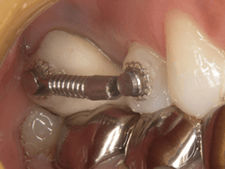

症例.5 健康な歯を引っ張り出す

|

|

| 虫歯で歯が少ない状態です。 歯と歯茎の境目が不明瞭です。 |

ゴムの力を使って歯を歯茎より上に引っ張ります。 |

|

|

| 健康な歯が歯茎から顔を出しました。 | 精度の高い被せ物が入れられました。 |